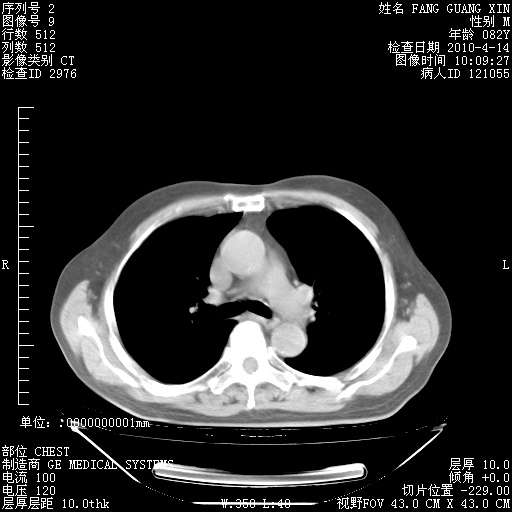

4月28日肺部CT——再次出现类似去年5月9日——透光度降低,(影像科认为)“间质性”改变。

4月28日肺部CT——再次出现类似去年5月9日——透光度降低,“间质性”改变。